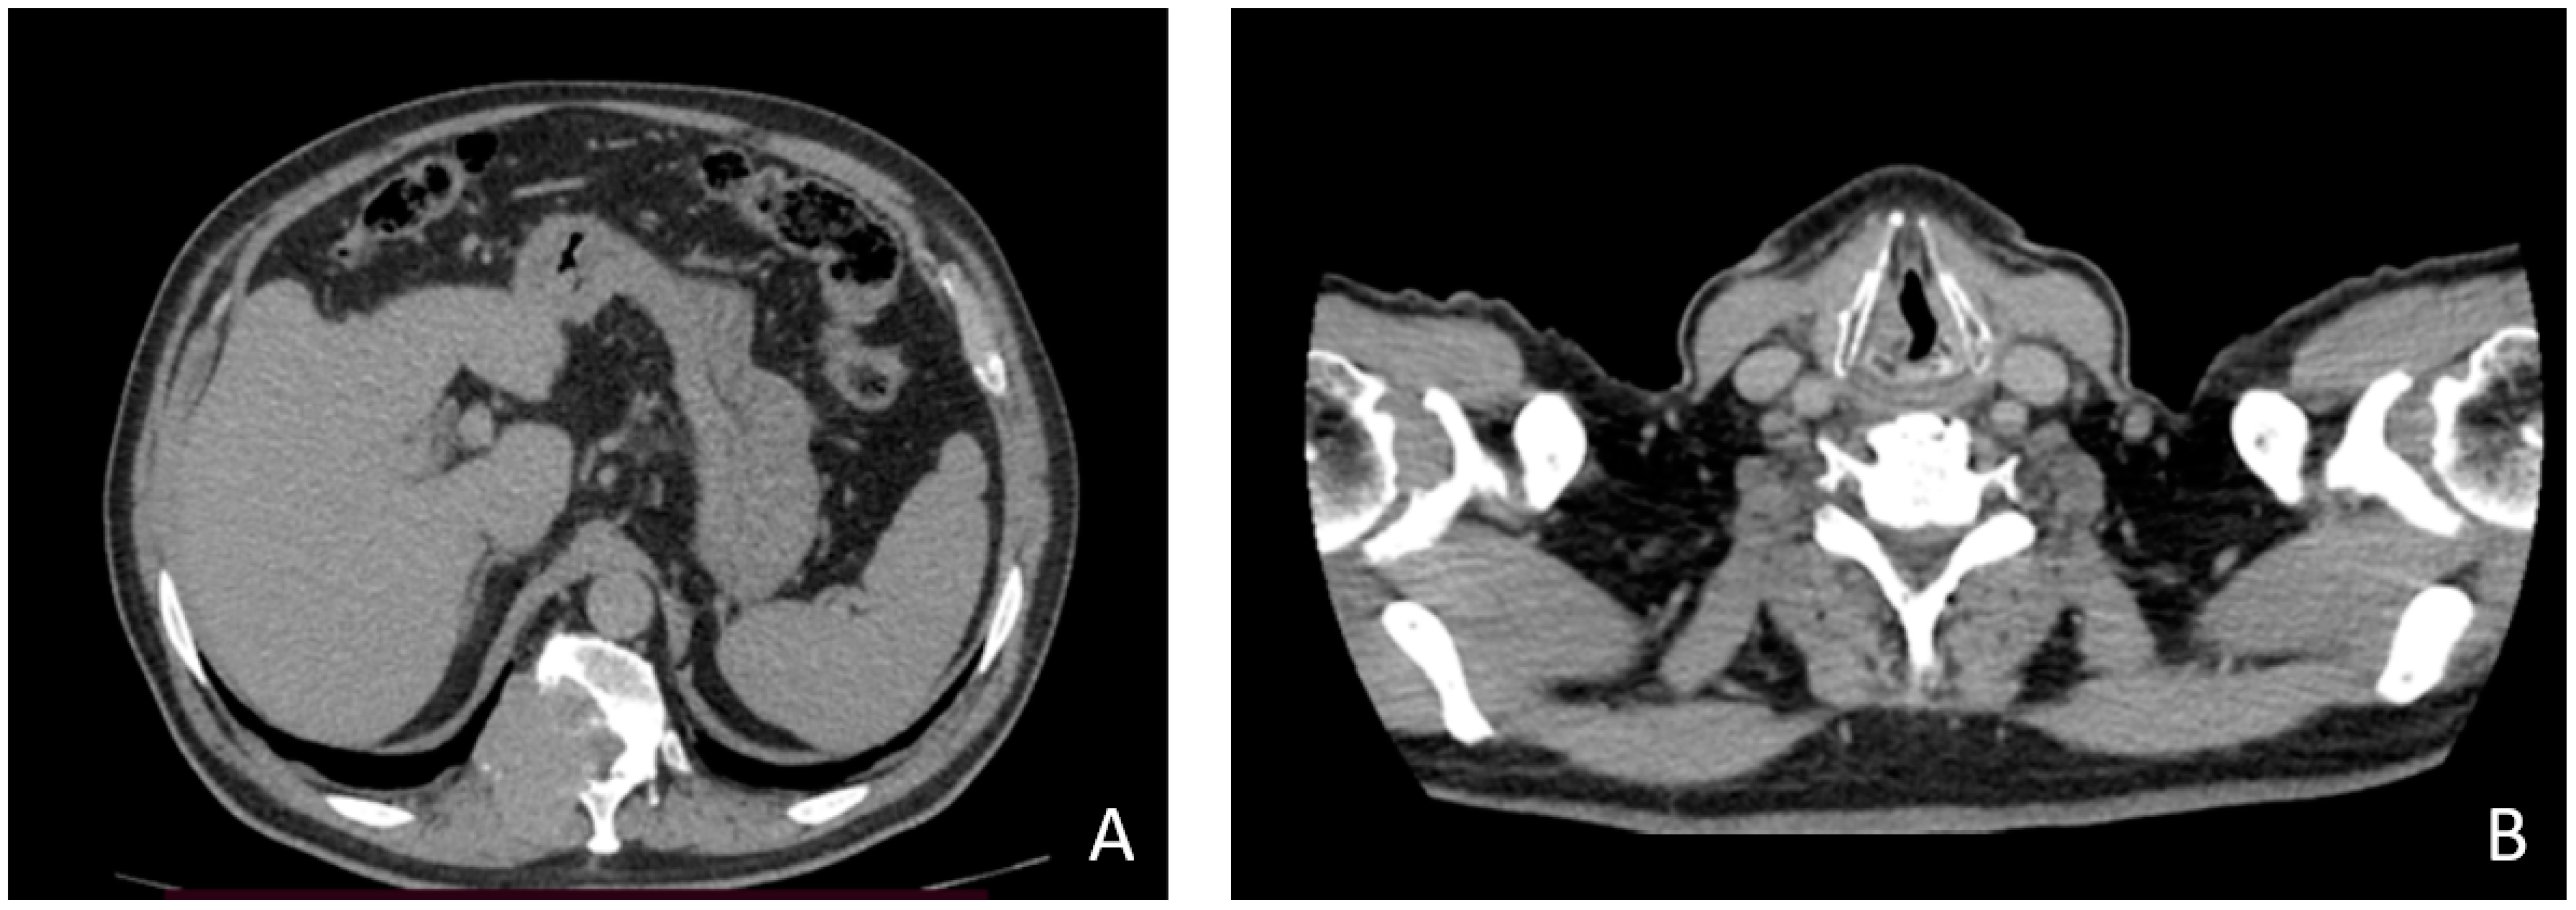

2. Case Description